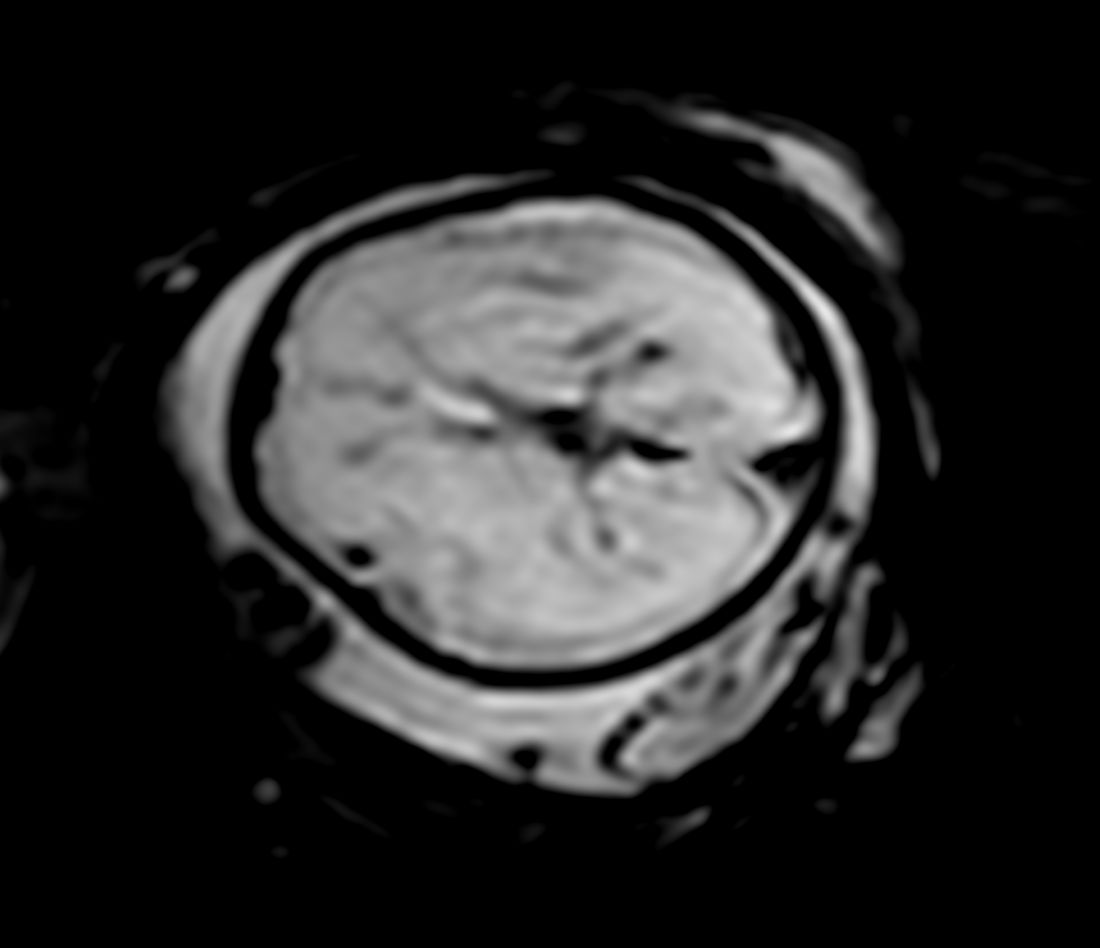

Axial T2w TSE single shotCompressed SENSE